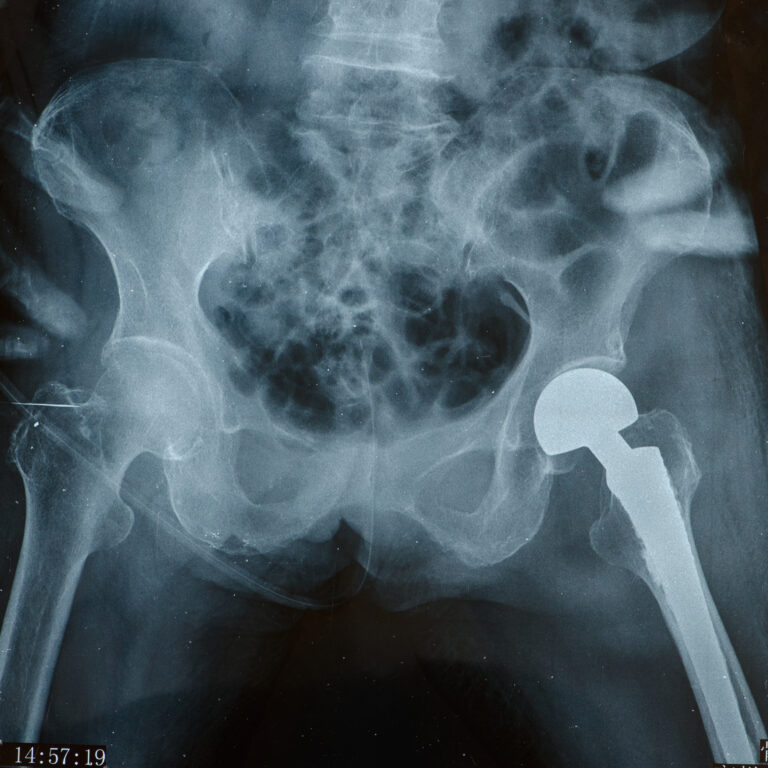

Our orthopedic surgeons are skilled in both minimally invasive techniques and complex surgical reconstructions, so we can tailor the solution to the severity of your condition. We always consider conservative treatments first — physical therapy, medications, or injections — and many of our patients improve without surgery.

But if you do need an operation, rest assured you’re in capable hands. We prioritize techniques that minimize incision size, reduce pain, and speed up recovery — like arthroscopy for many joint repairs. We’ll walk you through the entire process: what the surgery entails, how to prepare, and what recovery will look like.